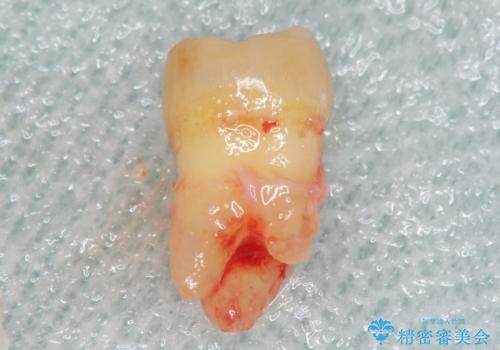

保存不可能な奥歯(左下6)を抜歯し、機能していない親知らず(左下8)の移植を行いました。

精査したところ奥歯(左下6)が破折しており、保存不可能と診断されました。

- 適応範囲に制限があります(健康な親知らず・移植歯が必要など)